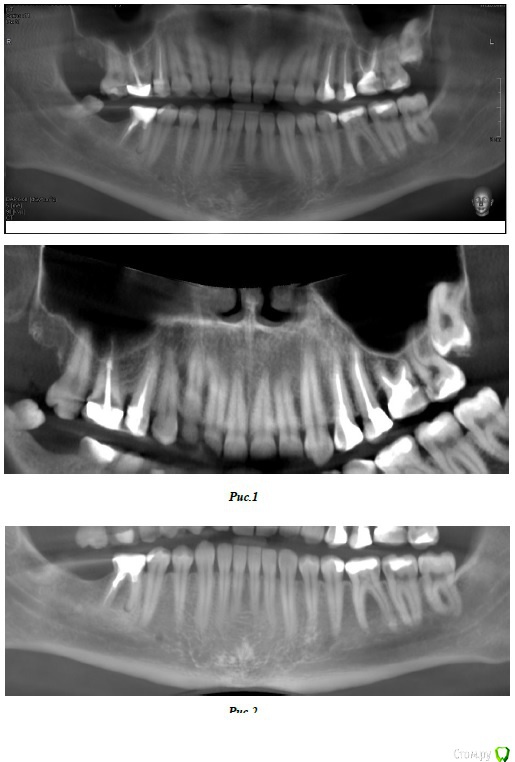

bbss Опубликовано 11 июля, 2018 Поделиться Опубликовано 11 июля, 2018 (изменено) Здравствуйте. Подскажите пожалуйста, с чего стоит начать, учитывая мои общие симптомы (тяжесть в затылке, иногда как туман (или ощущение в голове как при температуре, когда лечь нужно, плюс как будто жар в затылке), боль при жевании в затылке (говорении, кажется, что болит, когда языком двигаю), звон в левом ухе (сейчас что-то хрустит в челюсти слева, но до этого не было такого), при движении глаз дискомфорт. Бывает дискомфорт в области переносицы, межбровной области, как будто распирает или отек (особенно при наклоне головы) .Возможно, зубы в этом не виноваты, конечно.Прикладываю описание кт и общее фото (еще есть отдельные картинки, если нужно, то их тоже выложу). Кратко диагноз:Кариес 3.6Хронический периодонтит 4.6 (этот зуб у меня был пролечен рез-форм, зимой прошлого года отпала пломба, врач попыталась пройти каналы, но получилось только 1 пройти, два других - не вышло).КЛКТ признаки склерозирующего остеита зуба 3.6КЛКТ -признаки внутренней резорбции зуба 2.6Частичная обтурация корневых каналов 1.5,1.6, 2.4,2.6 без признаков периапикальных изменений.Ретенция зуба 2.8 Еще в описании почему-то нет 4.8., наверное упустили его. И хотела спросить, может ли быть так, что у меня идет перекос из-за пломб? Года 3 назад мне ставили пломбу на 2.6 и кажется на 2.5. После этой пломбы 2.6 были очень неприятные ощущения, как -будто это пломба мешает, зуб казалось очень стянут ( до пломбы таких ощущений не замечала), сходила снова туда же, мне врач его видимо подровнял, но это не помогло, пришлось в др месте переделать, стало получше, но все равно было ощущение, что что-то не то. Я еще подумала, что ощущение, что зуб стянут может быть возникло из-за чего-то, что пахло хлоркой. И похожее ощущение было с 4.8 (ставили пломбу). Спасибо! Изменено 11 июля, 2018 пользователем bbss Ссылка на комментарий